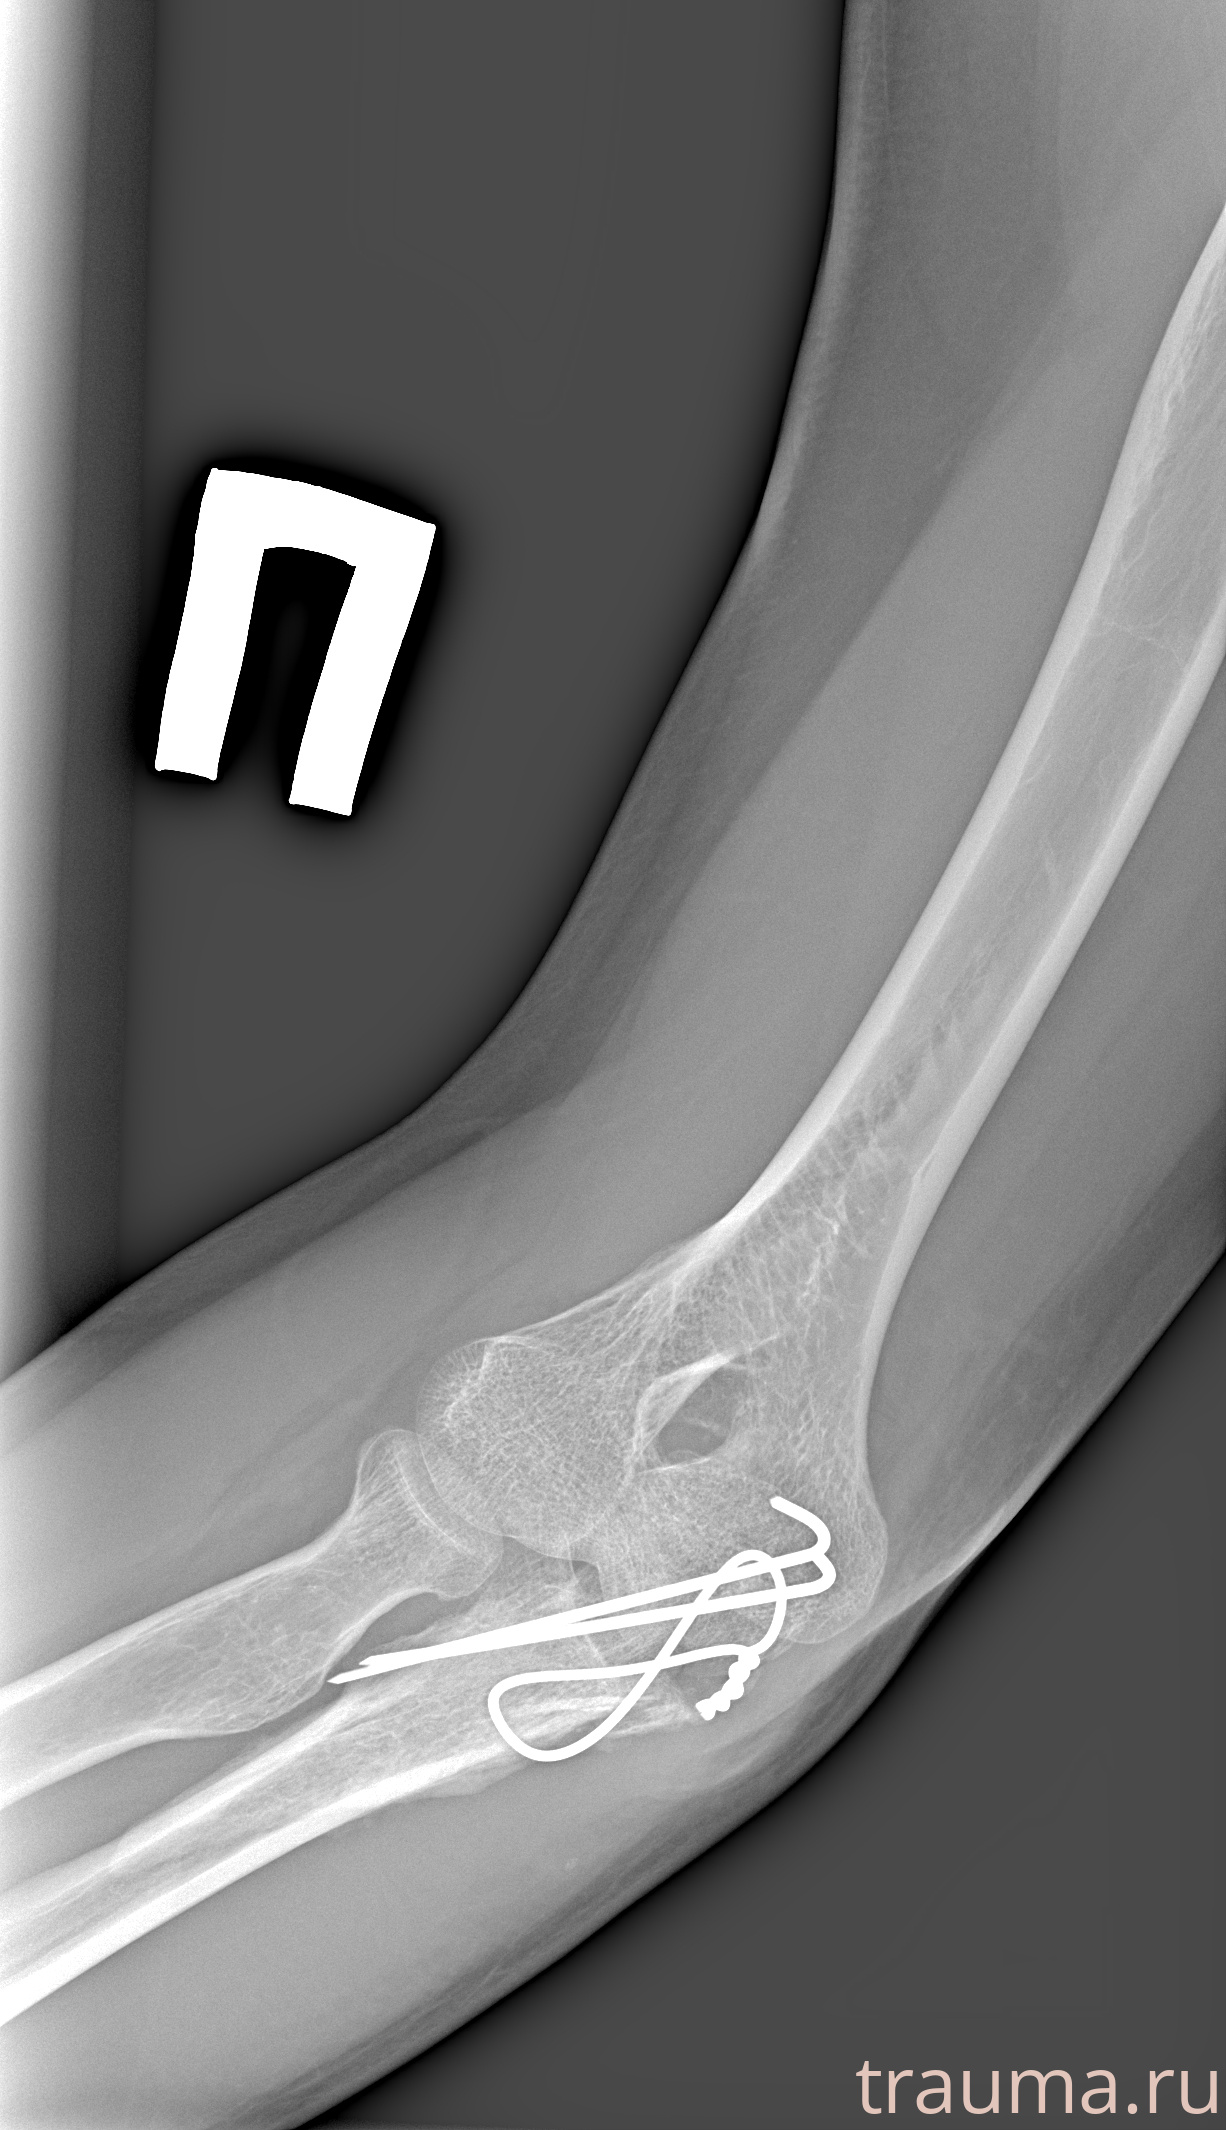

Рентген на дому: по вашему адресу приезжает врач-рентгенолог, травматолог-ортопед с мобильным рентгеновским аппаратом, проводит диагностику травмы или заболевания, делает необходимые рентгенограммы, дает рекомендации по дальнейшему лечению. Получить качественные снимки в домашних условиях возможно благодаря уникальной методике, разработанной МосРентген Центром для института  Склифосовского